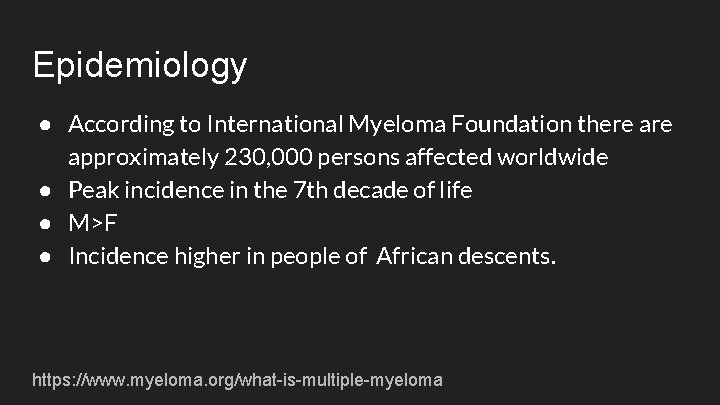

Epidemiology ● According to International Myeloma Foundation there approximately 230, 000 persons affected worldwide ● Peak incidence in the 7 th decade of life ● M>F ● Incidence higher in people of African descents. https: //www. myeloma. org/what-is-multiple-myeloma